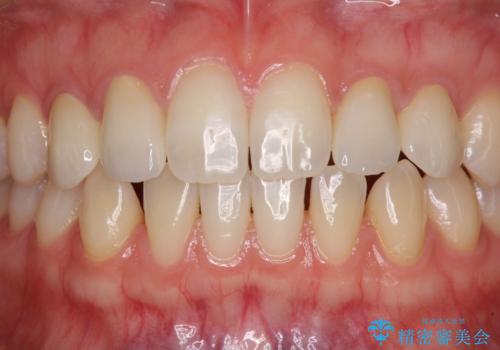

上顎歯列全体を後方移動させたことで唇に当たる感覚は改善され、更には上下の正中位置も合わせることができました。